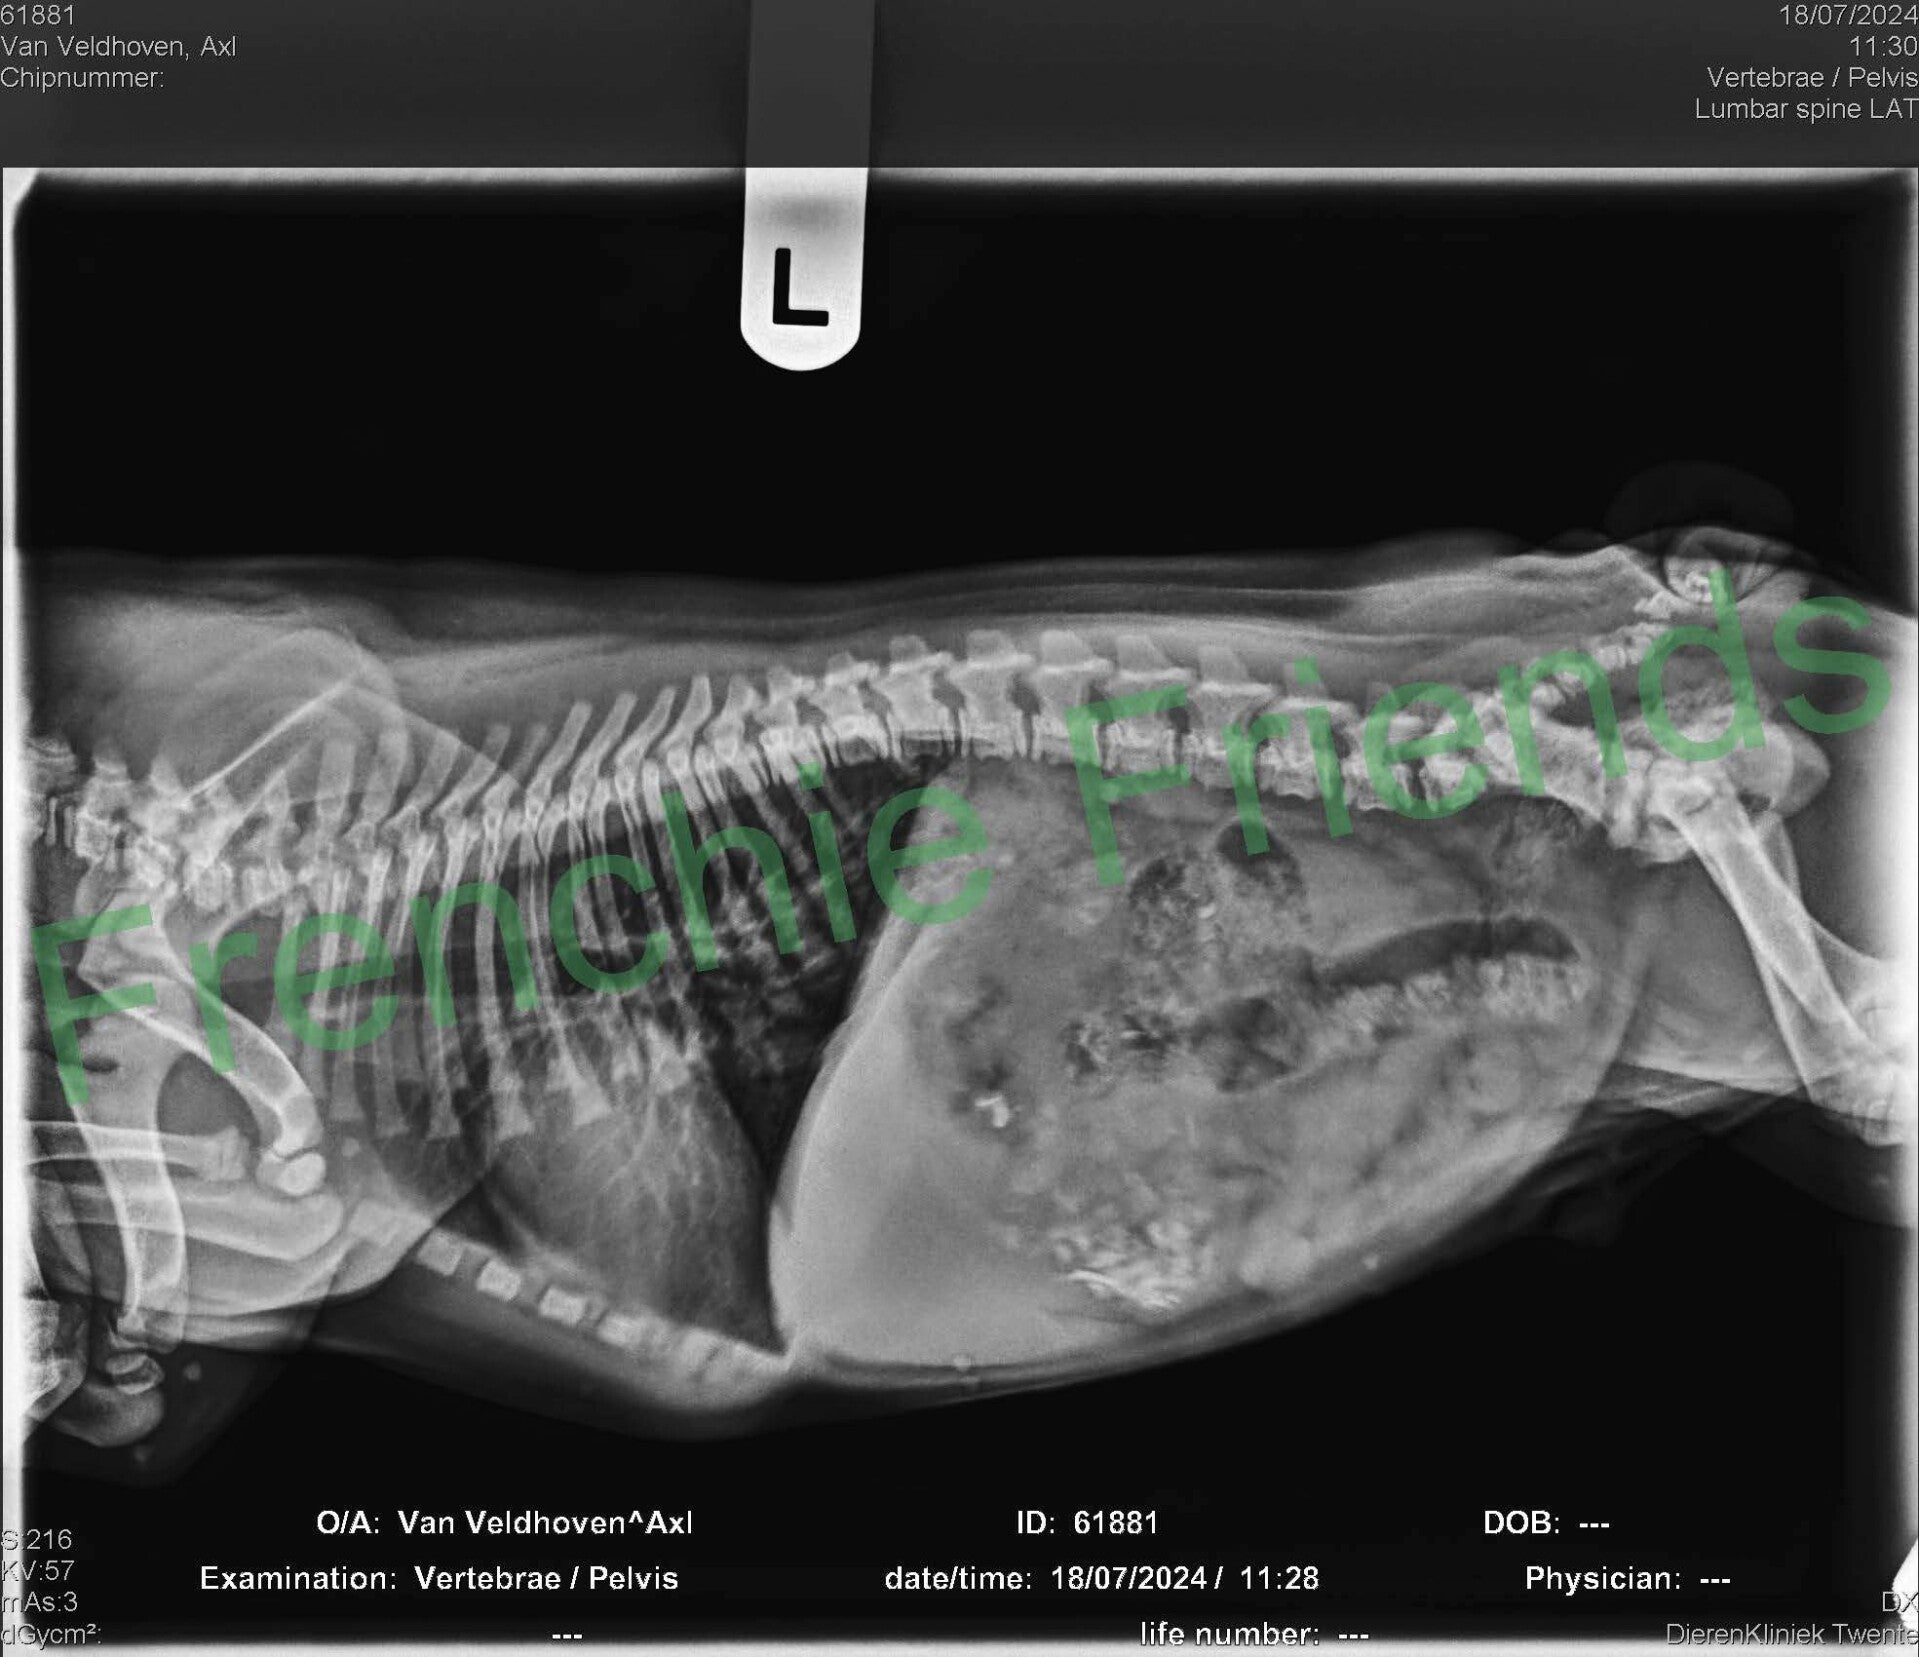

Op de röntgenfoto hadden we al gezien dat er 7 pupjes verwacht werden en alsof ze het al jaren zo deed perste Indy zonder problemen het ene na het andere pupje naar buiten. Bij nummer 5 werd het even spannend, maar mede dankzij mijn hulplijn met Esther, is ook dit pupje uiteindelijk goed en gezond ter wereld gekomen.

Het tempo ging inmiddels omlaag. Gelukkig wisten we door de röntgenfoto's dat we 7 pups konden verwachten. Om 23:25 uur kwam er nóg een fawn reutje, beduidend kleiner weer met een gewicht van 214 gram, Axl (Nu Appa). Appa woont bij Hanne in Antwerpen en wordt daar vreselijk verwend.